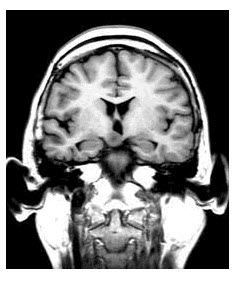

[单选题,共用题干题] [复合型非选择题]患者男,6岁,因“发作性不明原因发笑4年”来诊。发笑与环境不相宜,每次发作持续几十秒,并逐渐出现认知功能衰退。EEG:双侧前额和前颞的阵发性theta活动。其诊断可能是(提示行颅脑MRI检查,如下图。)()A .局部皮质发育不良B . 遗传代谢性疾病C . 结节性硬化D . 下丘脑错构瘤E . 海绵状血管瘤F . 胶质瘤

A . 其诊断可能是(提示行颅脑MRI检查,如下图。)()